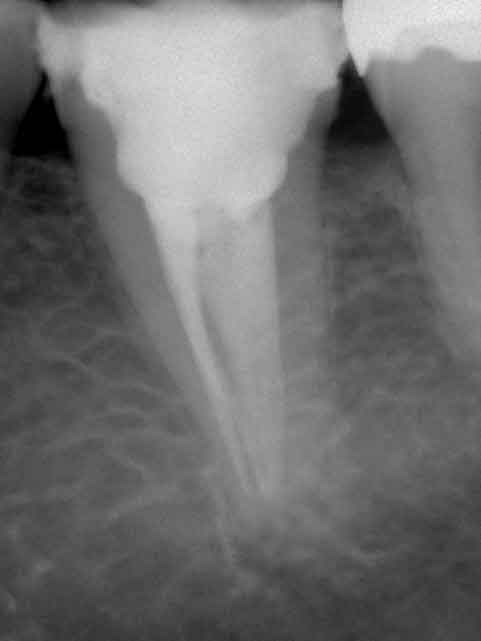

Zahnmedizinische röntgenologische Untersuchung (Bild 1):

Ø      Röntgenopaque superfizielle Füllung mod

Ø      Pulpakammer großzügig aufbereitet

Ø      Verdacht auf sehr enge oder sogar obliterierte Wurzelkanäle

Ø      Verdacht auf Perforation des Pulpakavumbodens